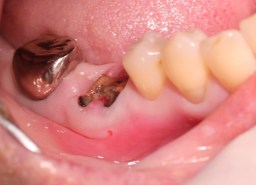

右下(46番)根破切

カルテ番号120106

同日抜歯、抜歯窩に唾液が入らないよう

に滅菌ガーゼをおきます。

↓抜歯した歯